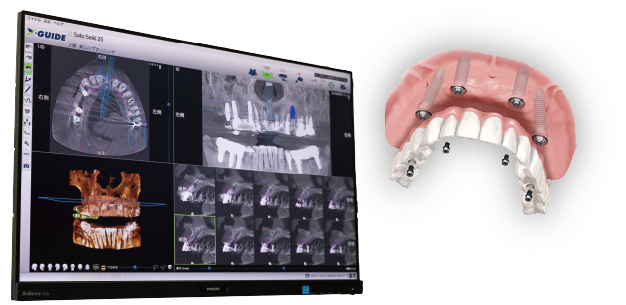

オールオン4

インプラント専門治療

インプラント専用のオペ室を備えた

マモインプラントクリニックで、

精密な治療をお届けします。